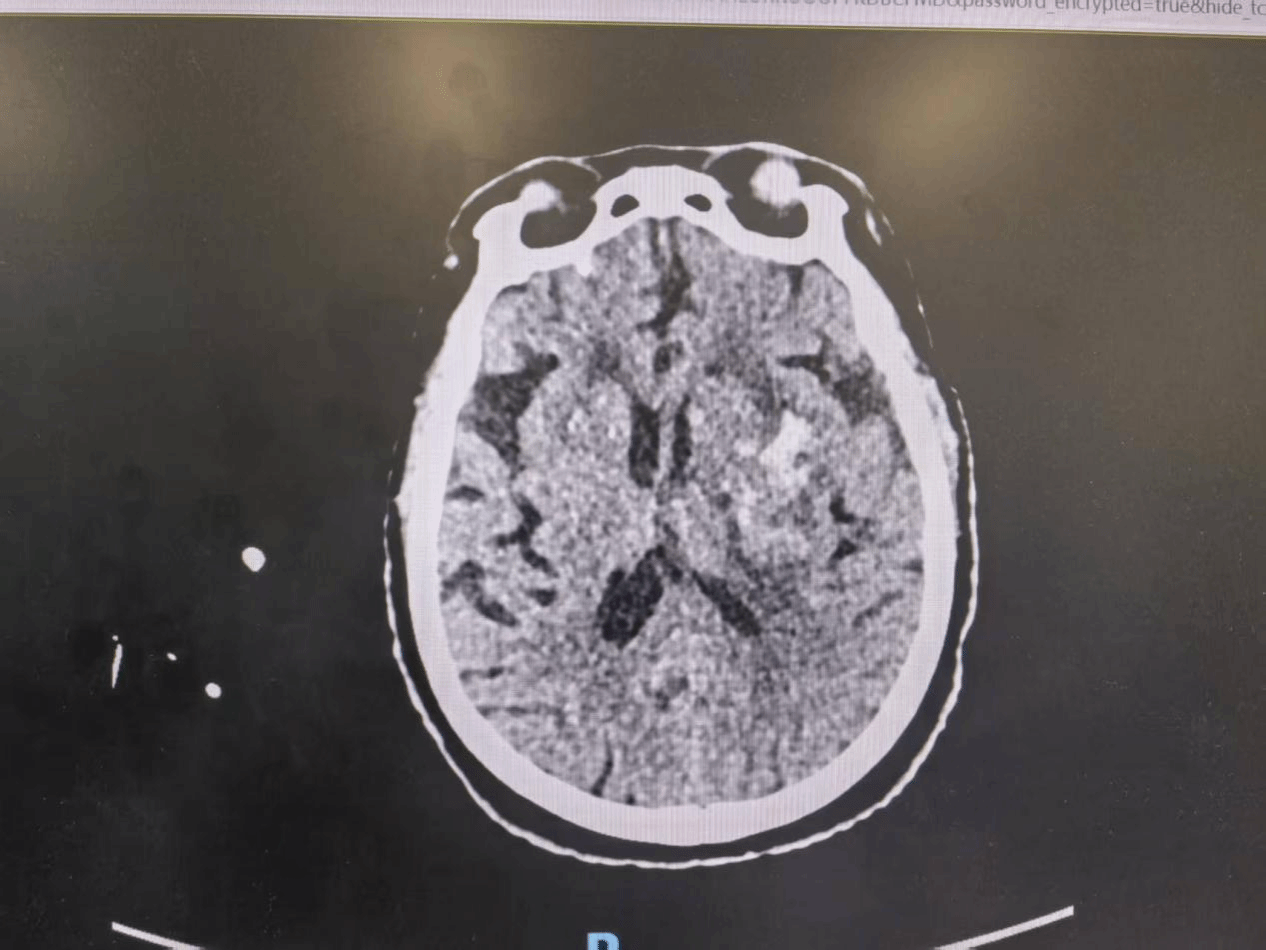

近日,西安市第九医院神经外科二病区收治一位87岁女性患者。家属发现其突发意识障碍,急呼120送至我院。急诊头颅CT提示:左侧基底节脑出血,出血量约40ml。患者既往有5年高血压史,未规律服药。

(术前)

基底节区出血位置深、病情凶险,且患者高龄、基础疾病多,传统开颅手术创伤大、风险高。时间就是大脑,如何在最短时间内有效清除血肿、降低脑损伤,是救治成败的关键。